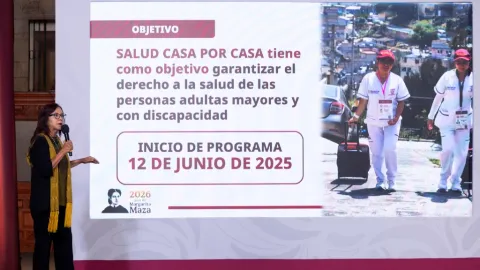

Salud Casa por Casa: A partir de 2027, programa permitirá recetar medicamentos para enfermedades crónicas a domicilio